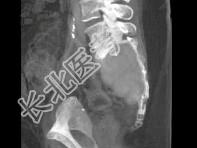

- 单项选择题患者60岁,如图所示, 该患者的鉴别诊断应除外 ( )

A、脊索瘤

B、浆细胞瘤

C、转移瘤

D、巨细胞瘤

E、以上都不是